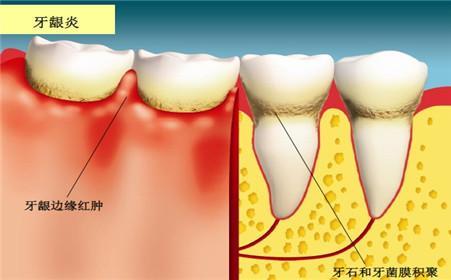

1、导致牙龈出血:牙龈炎

许多人吃辛辣刺激的食物,隔天早上刷牙发现牙龈肿胀,一旦刷牙就牙龈出血,其实就是上火引起的,本来已经是体内火气过盛,导致牙龈发炎,牙龈表皮比较脆弱,这时刷牙会造成二次伤害,刺激到牙龈,出血会更严重。